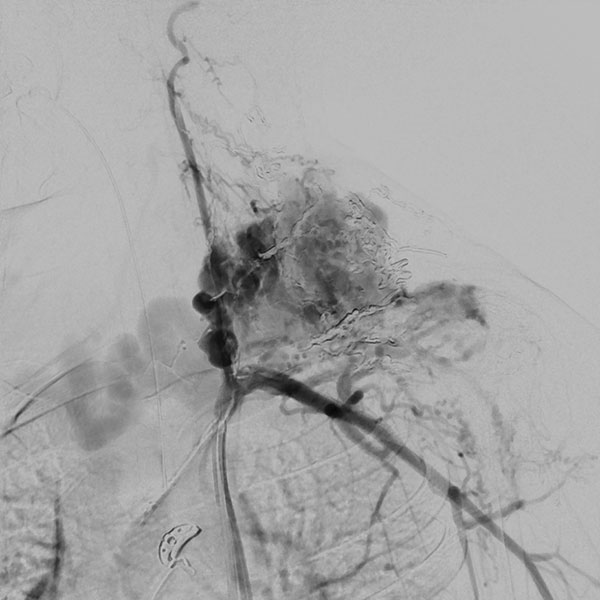

In der digitalen Subtraktionsangiographie (DSA) nach Injektion in die linke A. carotis communis stellen sich multiple, kaum zählbare zuführende arterielle Feeder dar, die den Nidus der arteriovenösen Malformation speisen. Sofortiger und direkter venöser Abstrom aus der Läsion.

Digitale Subtraktionsangiographie (DSA) nach Injektion in die linke A. subklavia. Es stellen sich ebenfalls unzählige zuführende arterielle Feeder dar, direkt aus der A. subklavia, aber auch multiple Zuflüsse direkt aus der linken A. vertebralis. Aufgrund der multiplen, feinen, kaum einzeln identifizierbaren arteriellen Zuflüsse ist eine rein transarterielle Embolisation technisch nicht möglich und auch nicht zielführend.